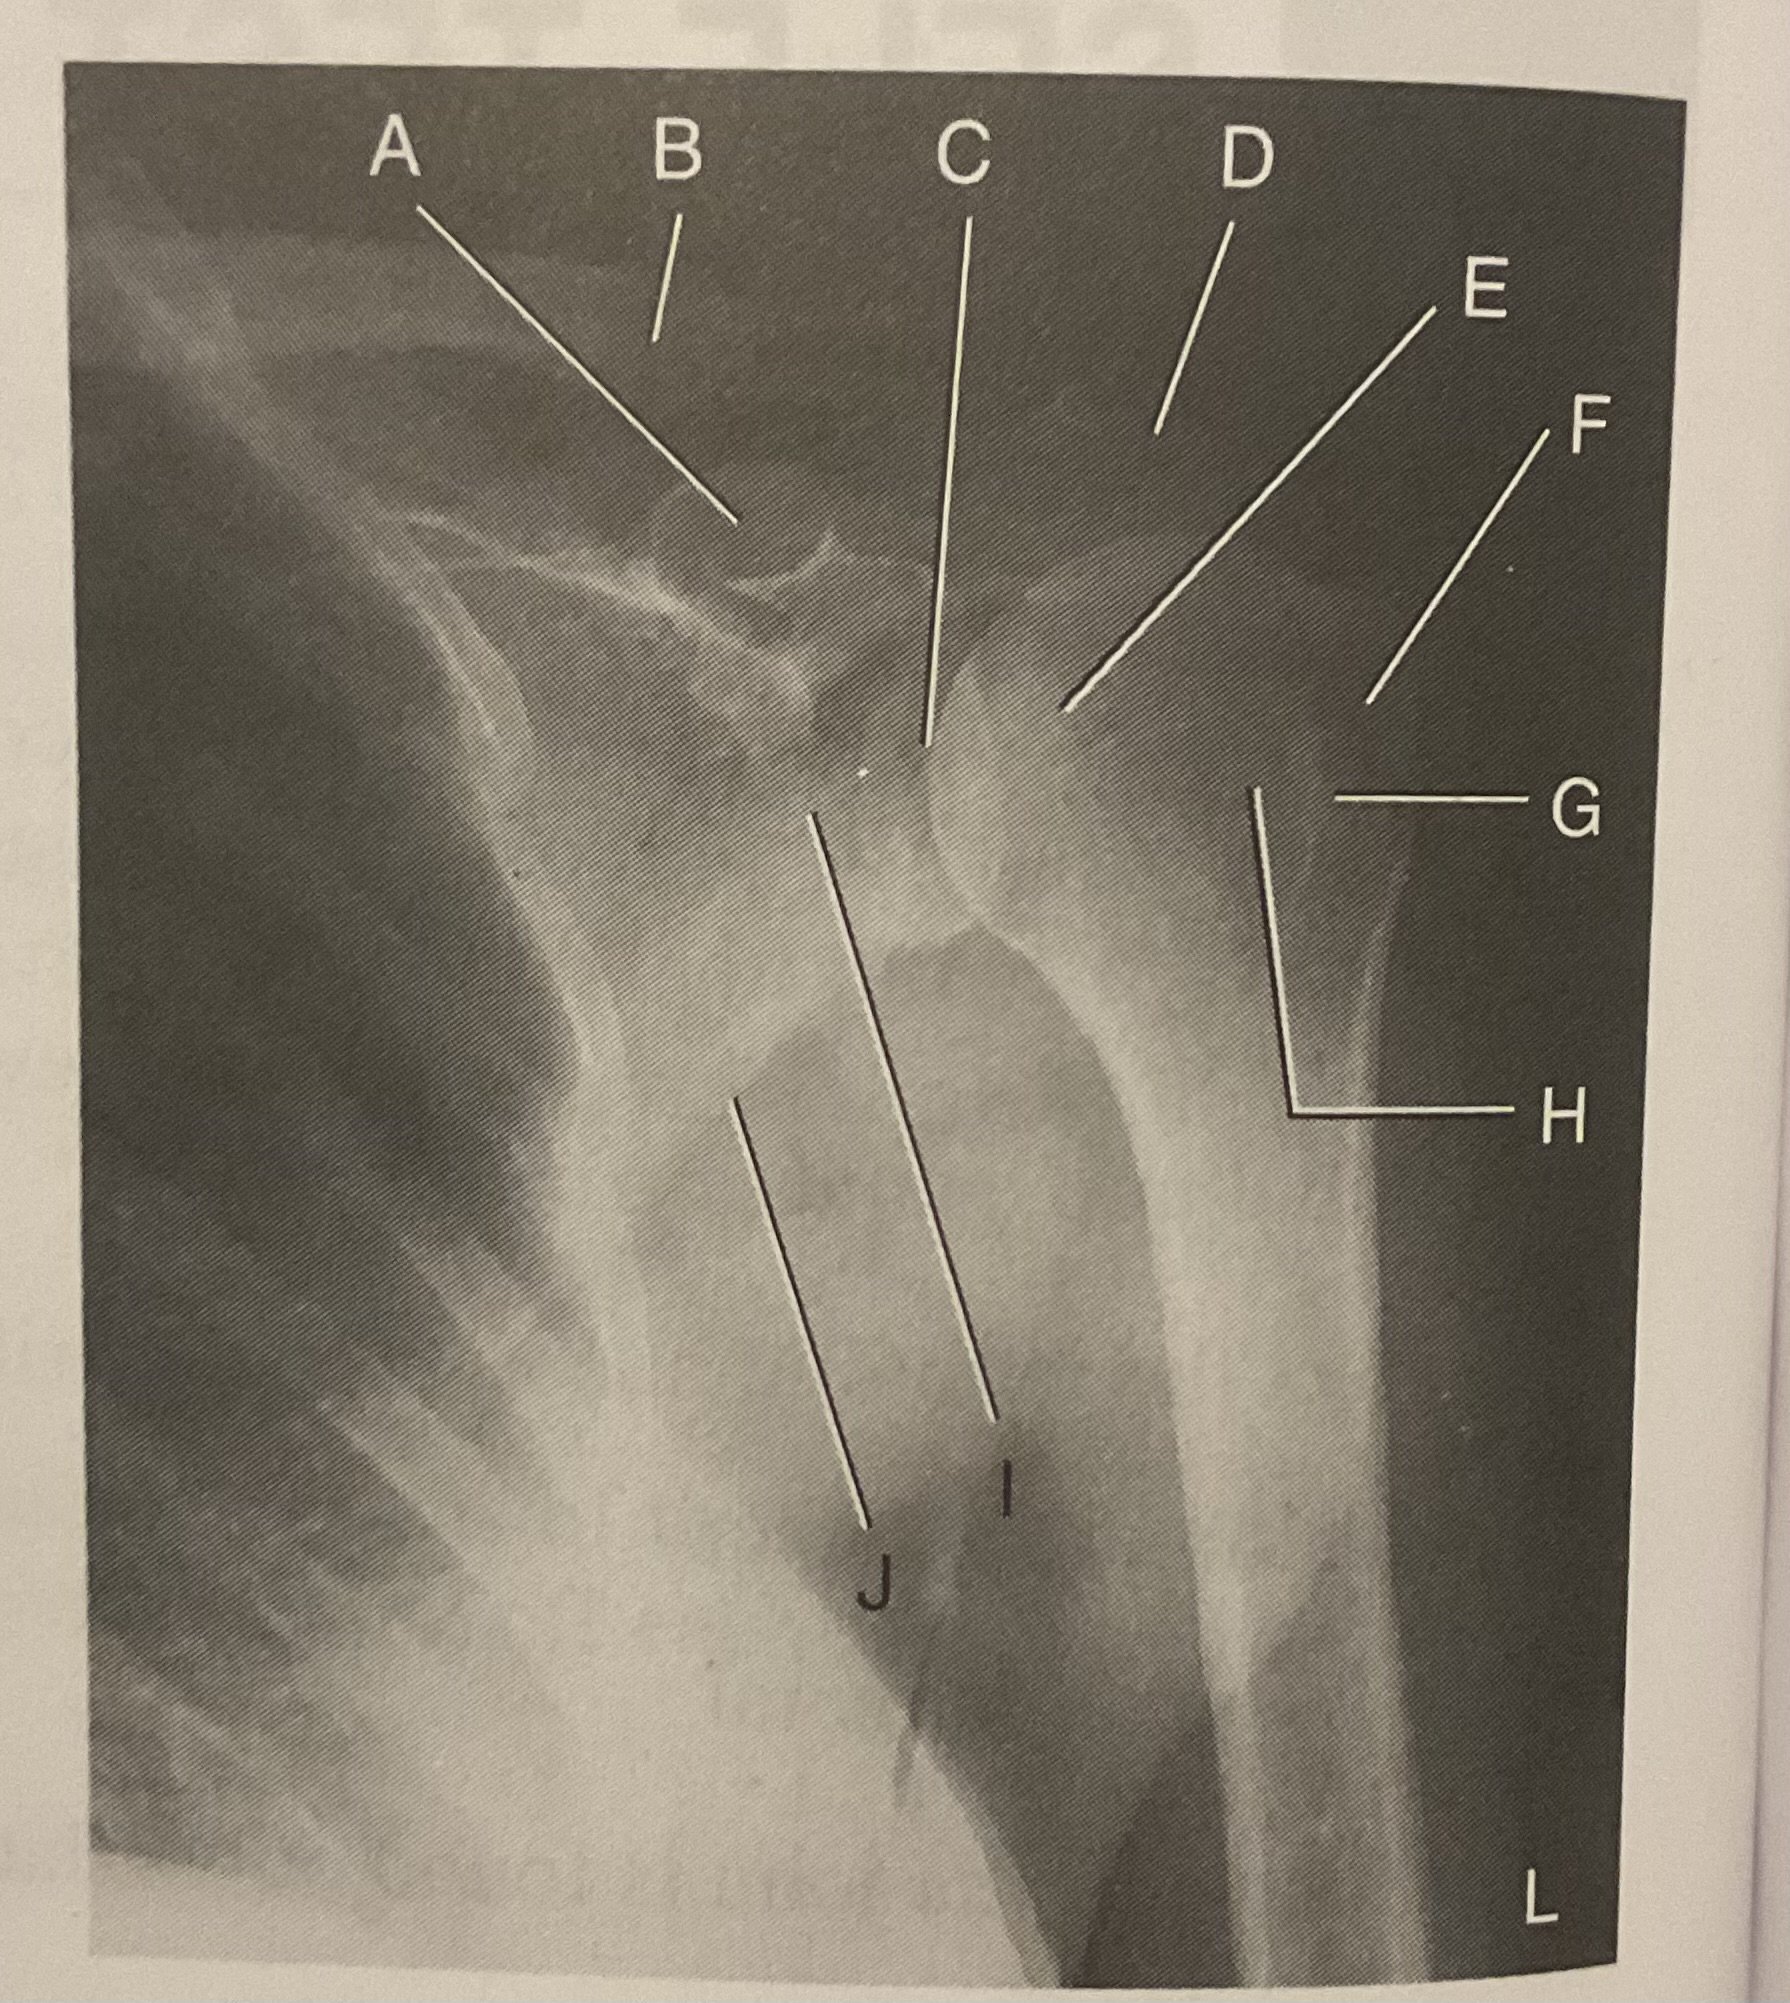

A?

Coracoid process

B?

Clavicle

C?

Scapulohumeral joint

D?

Acromion of scapula

E?

Head of humerus

F?

Greater tubercle

G?

Intertubercular sulcus

H?

Lesser tubercle

I?

Neck of scapula

J?

Lateral (axillary) border of scapula

What AP projection does this image represent?

External